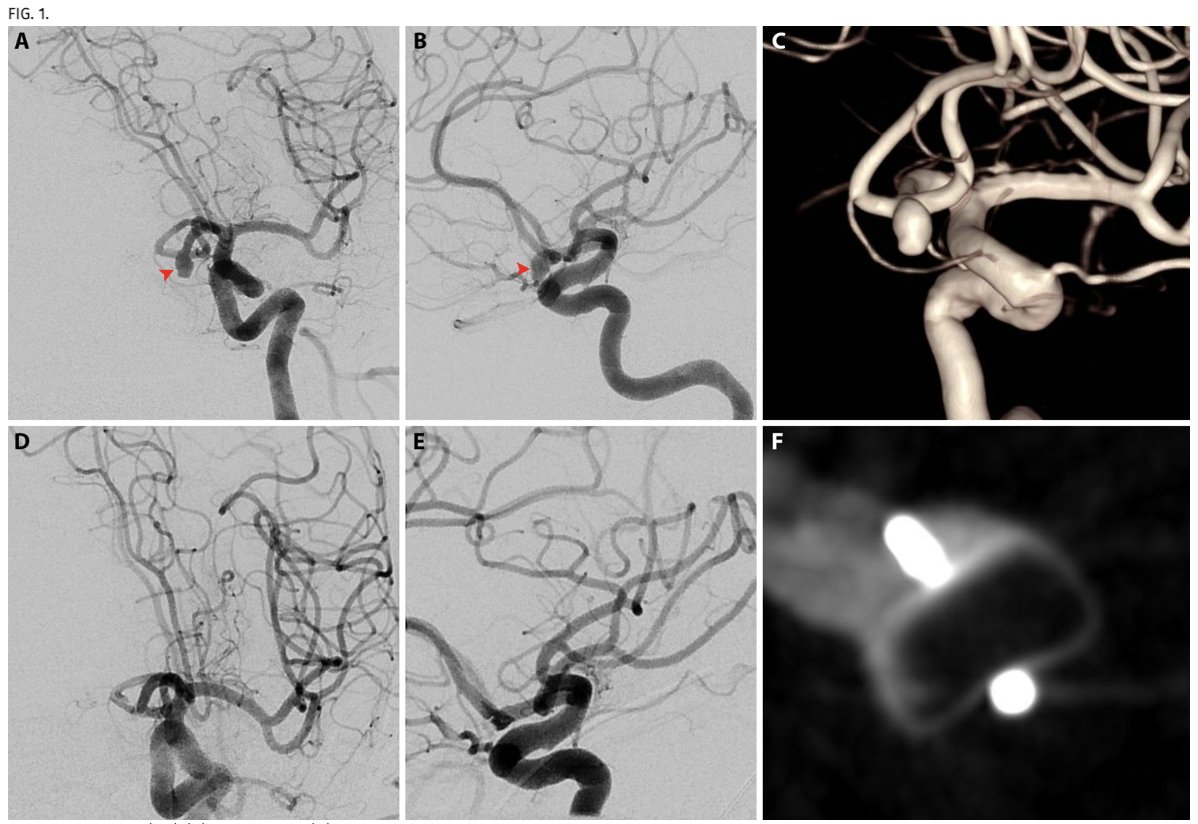

One of our project is to define pattern of indirect revascularization along with direct bypass in #Moyamoya My surgical strategy is combined direct and indirect Look at routine 6 months angio & Nova MR to identify key indirect anastomoses despite robust direct bypass CV Section

How do you treat this unusual large MCA #aneurysm with several blister looking irregularities? Double barrel #bypass using IMAX and STA with only distal occlusion will do it- proximal occlusion intentionally avoided to keep the last lenticulostriate open. CV Section Danielle Golub, MD, MSCI